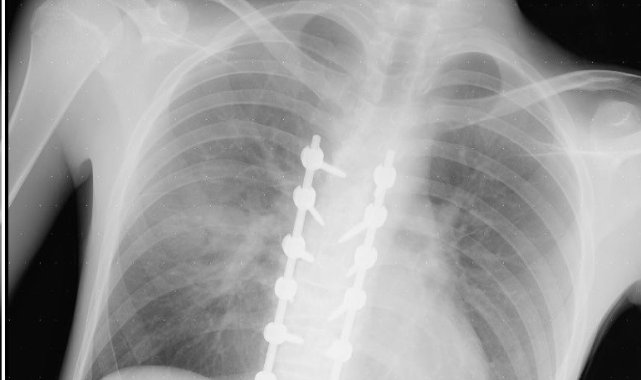

Eskişehir'de ara sokaktan çıkan otomobile çarparak ağır yaralanan 20 yaşındaki motosiklet sürücüsünün babası, oğlunun sağlık durumunun iyiye gittiğini söylerken, motosiklet kullanıcılarına da ekipman tavsiyesinde bulundu.25 Eylül günü Gündoğdu Mahallesi Cumhuriyet Bulvarı'nda yaşanan kazada, Şenel Sokak'tan bulvara çıkan Birol T. idaresindeki 34 HBF 007 otomobile, 20 yaşındaki Yusuf Gündoğmuş idaresindeki 26 AIZ 906 plakalı motosiklet yandan çarpmıştı. Kazada iki sürücü de yaralanırken, 20 yaşındaki motosiklet sürücüsünün sağlık durumu ağır olduğu öğrenilmişti. Kazadan sonra Eskişehir Şehir Hastanesi'nde uzun bir süre yoğun bakımda yatan ve birden fazla ameliyat geçiren Gündoğmuş, adeta ölümden döndü. Yoğun bakım tedavisi sırasında genç motosiklet sürücüsünün ailesinin sürekli dua ettiği öğrenildi.Oğlu ölümden dönen baba doktorlara teşekkür ettiGeçirdiği operasyonlar sayesinde kritik dönemi yavaş yavaş atlatan ve bilinci açılan Yusuf Gündoğmuş'un tedavisine sevk edildiği Eskişehir Osmangazi Üniversitesi Tıp Fakültesi Hastanesi'nde devam ediliyor. Genç motosiklet sürücüsünün 45 yaşındaki babası Hidayet Gündoğmuş, oğlunun iyileşmesi sebebiyle önce Allah'a sonra emeği geçen doktorlara minnettar olduğunu dile getirdi. Hem Eskişehir Şehir Hastanesi'nde hem de Eskişehir Osmangazi Üniversitesi Tıp Fakültesi Hastanesi'nde doktorların oğluna iyi baktığını söyleyen baba Gündoğmuş, oldukça mutlu olduğunu dile getirdi. Oğlu gibi kendisinin de motosiklete tutkun olduğunu söyleyen Hidayet Gündoğmuş, kaza görüntülerini izlediğinde ekipmanın ne kadar önemli olduğunu bir kez daha anladığına dikkat çekti. Biri kız olmak üzere üç çocuk babası Gündoğmuş, kendi gibi motosiklet tutkunu olan çocuklarına ekipman kullanmayı ısrarla söylediğini ve Yusuf Gündoğmuş'un da ekipmanları sayesinde hayatta kaldığını ifade etti"Rabbim kimseye yaşatmasın"Konuyla alakalı konuşan Hidayet Gündoğmuş, "Şükürler olsun, her gün daha iyiye gidiyoruz, daha iyiyiz. Şehir hastanesiyle ameliyatlarımız bitti. Oradaki doktorlarımıza çok teşekkür ederim, çok ilgilendiler. Tıp fakültesindeki plastik cerrahide estetik ameliyatlarımız var. Allah'a şükür her gün daha iyiye gidiyoruz. Çocuğumuz ayağa kalktı, sağlığı yerinde. Kaza anını gördüğümde anlatamam; kendim Diyarbakır'daydım, uzun yoldaydım. Rabbim kimseye yaşatmasın. Kötü bir duygu; çok şey demek isterim. Ben kendim de motor kullanıyorum. Bizde aile boyu hepimizde motor var. Kendim 18 yaşından beri kullanırım. Şükürler olsun bugüne kadar bir kazam olmadı. Çocuklarıma istedikleri motoru aldım. Amcalarında da var, amcasının çocuklarında da var. Bizim Eskişehir'imizin halkı motora karşı biraz daha duyarsız. Motor kullanan arkadaşlarımız, kardeşlerimiz de cahil. Arabaların sağından soldan trafikte çok geçerim, "geçivereyim" gibisinden hareketler var. Biz halk olarak yaya iken trafikteki taşıtlara kızarız, arabadayken yayalara kızarız. Halk olarak çok bencil bir toplumuz. Eğitim desem eğitim değil, kültür desem kültür değil. Herkes kendi çıkarları veya bencil davranışları yüzünden trafikte birçok kaza görüyoruz. Her gün kazalar oluyor. Motora binen özellikle gençlerimizi ve kuryelerimizi acele etmemeleri konusunda uyarıyorum" diye konuştu."Bedeli biraz ağır oldu ama şükürler olsun Rabbime"Trafikte sıklıkla seyreden kuryeler başta olmak üzere motosiklet kullanıcılarını uyaran Gündoğmuş, şöyle devam etti;"Özellikle kuryeler, insanların siparişlerini iki dakika önce götüreceğim diye kendi hayatlarını, kendi canlarını riske atmasınlar; sevdiklerini üzmesinler. Biz böyle ağır bir kaza yaşadık; keşke yaşamasaydık. Bedeli biraz ağır oldu ama şükürler olsun Rabbime. Daha iyiyiz. Her gün daha iyiye gidiyoruz. Herkes dikkatli olsun. Yani motora binenler de araçlara karşı dikkat etsinler. Araç kullanan vatandaşlarımızın da motorları görmelerini istiyorum.""Evladımız gayet iyi, sağlıklı, yerinde"Oğlunun tedavi sürecini anlatan Hidayet Gündoğmuş, şunları kaydetti:"Beş gün entübe edildi. Ne olacağı belli değildi çıkmama ihtimali vardı. Şükürler olsun doktorlarımız ve Rabbim sayesinde entübeden çıktık. Hatta ciğerin birisinde infilak vardı; ciğer sorunumuzdan dolayı özellikle yoğun bakımda entübediydik. Beş günün sonunda ciğerleri toparlamaya başladı; entübeden çıkarttılar. Solunumu normale döndü. Sırayla sağlığı yerine gelmeye başladı. Bir hafta sonra kolundan ameliyat oldu platin koydular. Omurilikten ameliyat olduk. Omuriliğinde ilk röntgende tek kırık gördüler; üç kemiği birbirine bağlayacaklardı. Sonradan ikinci röntgende üç kırık olduğunu gördük; yedi kemiği birbirine bağladılar. Omuriliğe platin takıldı. 14 tane civatamız var. Şükürler olsun doktorlarımıza, Allah razı olsun. Evladımız gayet iyi, sağlıklı, yerinde. Artık işte suratta, çenede, burunda, elmacık kemiklerinde parçalı kırıklarımız var. Osman Gazi Fakültesi'nde Allah'ın izniyle buradaki hocalarımıza, önce Rabbim'e sonra hocalarımıza emanet çocuğumuz. İnşallah daha iyi olacağız; ben kendi adıma söylüyorum. Çocuğuma, her motora bindiklerinde sürekli kask ve montlarını giymelerini tembihliyordum. Giymediklerinde fırça atıyordum. Eskişehir'de birçok yerde tanınırız, tanırlar. Sevenimiz, eşimiz, dostumuz çok; uyarırlar, telefon gelir, haber verirler. Her duyduğumda, gördüğümde söylerim. Sağ olsun, çocuğum da o gün beni dinlemiş, kaskını takmış. Şükürler olsun ki takmış; takmasaydı o gün, o kazada belki çocuğumuzu kaybederdik."